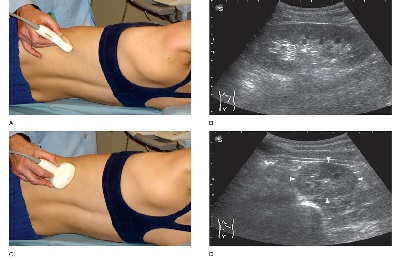

Особенности проведения исследования

Как уже было сказано выше, процедура ангиосканирования в большинстве случаев сочетается со стандартным УЗИ. Это позволяет произвести комплексную оценку органа и его кровеносного русла, что в разы повышает информативность диагностического мероприятия.

Процедура абсолютно безболезненна, по продолжительность занимает до 30 минут, в редких случаях – до 40 минут. После пациент сможет забрать заключение, в котором будет указан результат проведенного исследования.